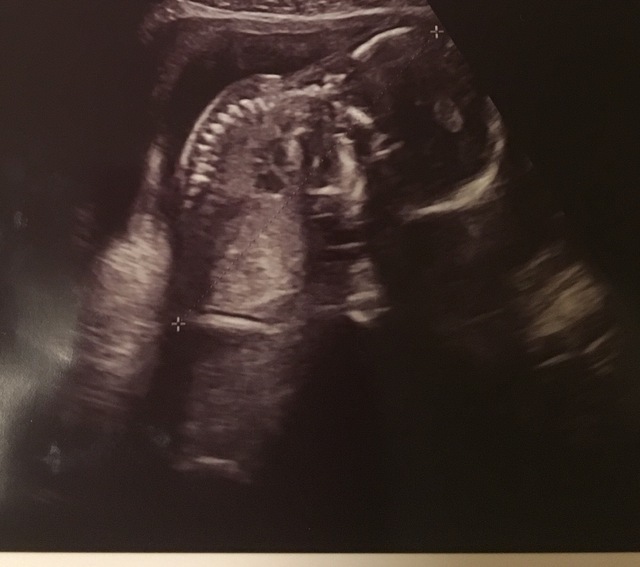

18週3日(18w3d・女の子)|よーちゃん、! さん(27歳)

エコー写真撮影時のエピソード:

妊娠7ヶ月のプレママです。

妊娠6ヶ月に入るまで、私は胎動を全く感じませんでした。

このエコー写真の時期はもちろん胎動がなく、赤ちゃんが無事に生きているのかとても心配でした。

そんな時エコー写真で赤ちゃんの背骨をはっきり見ることができて、大きくなってきているのだなあととても嬉しくなりました。

赤ちゃんってだんだんと人間らしくなっていくのですね。

パパにエコー写真を見せた時、これが背骨だよっと教えると、すごいなあーとびっくりしていました。

産まれるまであと3ヶ月です。

赤ちゃんに会えるのが楽しみです。